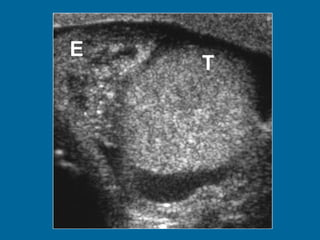

Tumor del seno endodermico mass.  (a)  Longitudinal US scan of the left hemiscrotum shows a solid tumor  (T)  replacing the entire testis. The cystic areas (arrowheads) represent tumor necrosis.

Tumor del senoendodermico mass. (a) Longitudinal US scan of the left hemiscrotum shows a solid tumor (T) replacing the entire testis. The cystic areas (arrowheads) represent tumor necrosis.